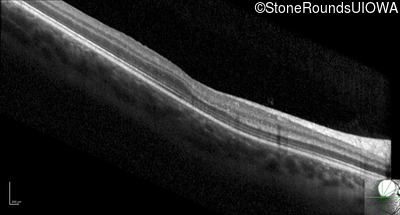

Optical Coherence Tomography - Right - 20/40 +2

Exemplar / OCT Stack